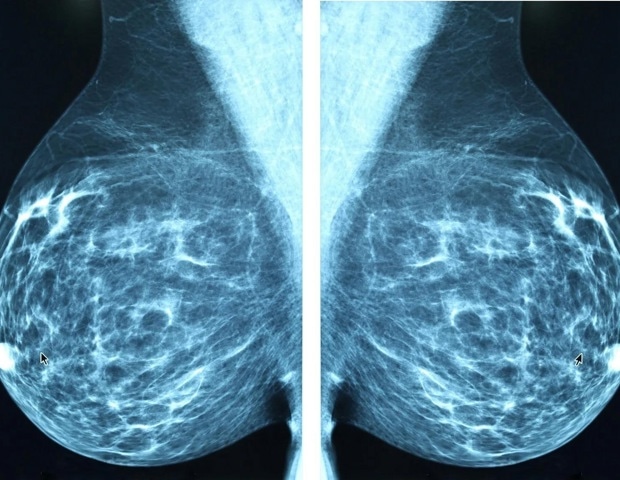

Η αφαίρεση μέρους ή ολόκληρου του μαστού κατά τη διάρκεια της θεραπείας του καρκίνου του μαστού είναι μια πιθανή εξέλιξη για αρκετούς ασθενείς. Οι διαδικασίες αποκατάστασης συχνά περιλαμβάνουν προσθετικά εμφυτεύματα ή μεταμοσχευμένο ιστό από άλλες περιοχές του σώματος. Ωστόσο, ερευνητές που δημοσίευσαν τα ευρήματά τους στο περιοδικό ACS Applied Bio Materials ανέπτυξαν ένα πρωτότυπο injectable υλικό από ανθρώπινα κύτταρα, το οποίο θα μπορούσε να βοηθήσει στην αποκατάσταση του όγκου του μαστού μετά την αφαίρεση όγκων, προσφέροντας λιγότερες ουλές και ταχύτερη ανάρρωση σε σύγκριση με τις υπάρχουσες επιλογές.

Η νέα αυτή injectable πάστα προάγει την ανάπτυξη αιμοφόρων αγγείων και την αναδόμηση ιστών, διατηρώντας παράλληλα χαμηλή τη φλεγμονή και μειώνοντας την πιθανότητα εμφάνισης καψικής συστολής. Αυτό θα μπορούσε να καταστήσει την αποκατάσταση του μαστού πιο ασφαλή, λιγότερο επεμβατική και πιο προσβάσιμη, βελτιώνοντας έτσι τη μακροχρόνια άνεση και τα αισθητικά αποτελέσματα για τους ασθενείς.